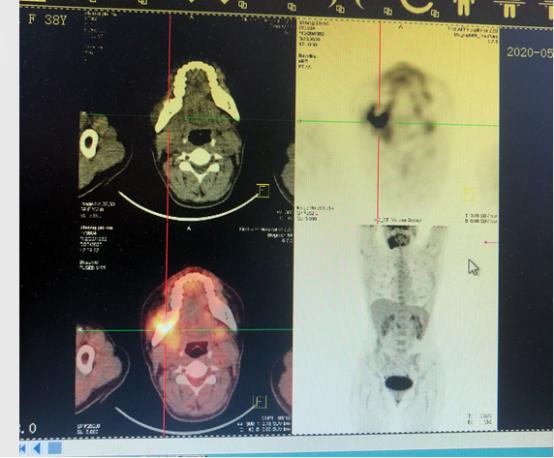

2020-05-20 患者PET-CT 显示:患者病情稳定。截图如下:

患者本次(2020-05-20)PET-CT 右侧下颌骨局部截图:

怀疑右侧下颌骨病变为骨转移,行病理穿刺。

结果证实患者右侧下颌骨病变不是骨转移,对症处理后出院。现患者一般情况良好,生活如常(此文写作时间2020-07-28)。